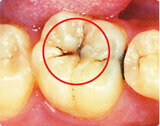

- 初期虫歯: 歯のエナメル質に小さな変色や斑点が現れます。この段階では痛みはほとんど感じませんが、歯の表面が酸によって溶け始めています。

- 中程度の虫歯: エナメル質がさらに侵食され、象牙質にまで達します。この段階で痛みを感じることがあります。

- 重度の虫歯: 虫歯が象牙質を越え、歯の神経にまで達します。痛みが強くなり、感染症のリスクが高まります。